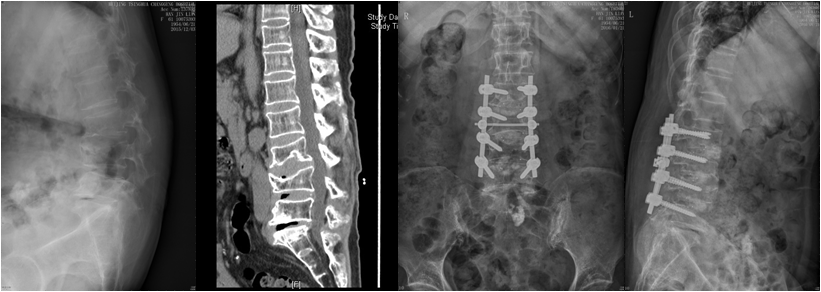

腰椎后凸畸形,矢状面失平衡,无法直腰行走;腰椎后凸截骨矫形融合固定

在肖嵩华主任的带领下,医院春节后先后收治4例较为复杂的脊柱侧弯患者。一例儿童先天性脊柱侧弯,半椎体合并分隔不全;一例腰椎退变性侧弯伴间盘源性腰痛;一例腰椎后凸畸形,矢状面失平衡,无法直腰行走;一例胸腰椎退变性侧后凸伴椎管狭窄,下肢疼痛麻木严重。

经完善三维影像学检查,脊柱专业组查房讨论,分别针对4例患者,制订个体化精准减压矫形方案,由肖嵩华教授主刀,宋飞主治医师和脊柱组医师配合,在连续的4个手术日,分别完成胸6半椎体切除胸廓成形矫形固定,腰椎后凸截骨矫形固定融合,退变性侧弯减压矫形固定融合,侧后凸减压截骨矫形融合固定,4台高难度手术均告成功。12岁的男孩是第一个接受手术的患者,男孩父母的心理压力非常大,待医师走出手术室,告知手术成功时,一直坚强的母亲眼泪瞬间流了下来,“这场手术把孩子的命运带回了正常的轨道。”

患者脊柱畸形得到纠正,伴随的椎管狭窄压迫神经等症状也得到彻底根治。困扰患者多年的躯干外形异常和神经功能障碍一去不复返。术后2-3天,4位患者均可下地,“腰杆子直起来了”;“大腿不疼不麻,能正常走路了”;“身高增加了”,脊柱畸形患者术后效果良好,可谓:新年开了个好头。